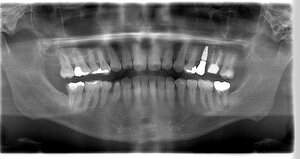

レントゲン写真

- Before

- After

| 年齢 | 40代・女性 |

|---|---|

| 主訴 | 左下6 |

| 治療内容 | インプラント埋入 |

| 治療費 | インプラント埋入料 440,000円 GBR(骨造成) 110,000円 サージカルガイド 55,000円 2次OPE 22,000円 静脈内鎮静麻酔 77,000円 合計 704,000円 (2023年5月現在) |

| 治療期間 | 7ヶ月 |

| リスク・副作用 | リスク・副作用 |

| 治療方針 | 左下6は歯根破折のため抜歯を行い、骨造成を同時に行いました。 骨ができてからインプラント埋入を行いました。 |

| 特記事項 | インプラントは人工物なので虫歯になることはありませんが、歯周病(インプラント周囲炎)にはなります。 インプラントを長持ちさせるには、毎日の歯磨きと合わせて、3~6ヶ月ごとの定期検診でのクリーニングが大切です。 |

| 担当者所見 | 歯を失ったまま放置してしまうと、周囲の歯に負担がかかるため、お口の中全体のバランスが崩れます。 インプラントは、骨に人工の歯根を埋め、被せ物を被せる治療法です。 外科的な手術が必要ですが、健康な歯を削ることなく、天然の歯と同じようにかめるようになります。 |